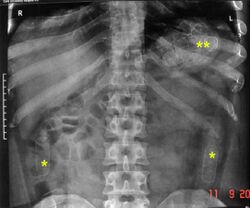

Plain radiograph of the abdomen of a drug "mule" showing drug capsules

Abdominal X-ray showing swallowed packages of cocaine.

Detection and medical treatment

Routine detection of the smuggled packets is extremely difficult, and many cases come to light because a packet has ruptured or because of intestinal obstruction. Unruptured packets may sometimes be detected by rectal or vaginal examination, but the only reliable way is by X-ray of the abdomen. Hashish appears denser than stool, cocaine is approximately the same density as stool, while heroin looks like air.[11][12]